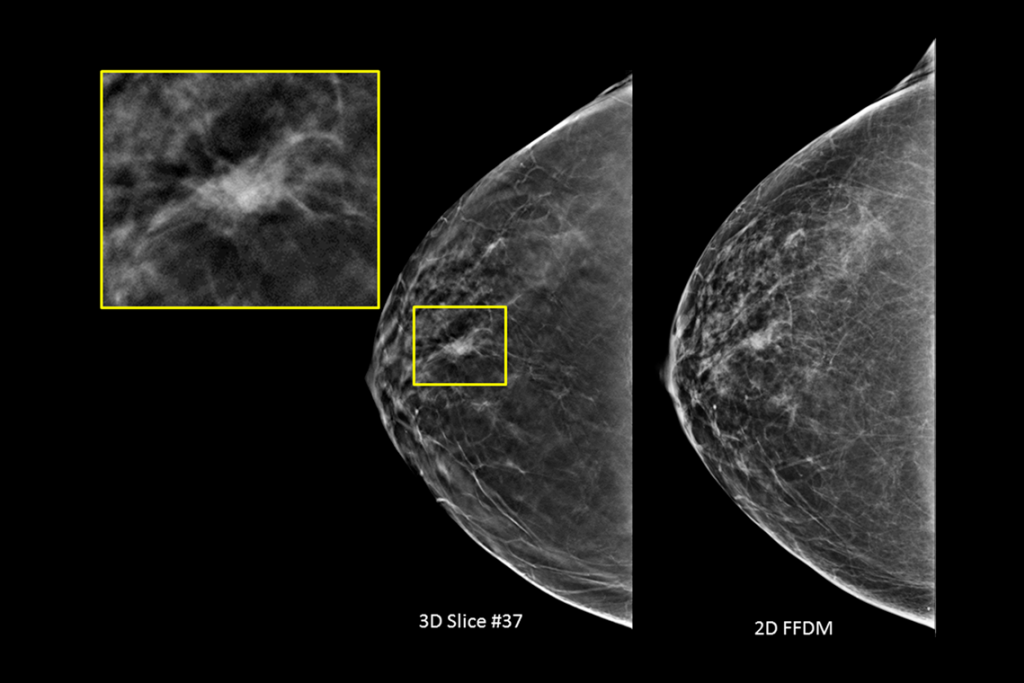

Imagens clínicas de mamografia com mama adiposa